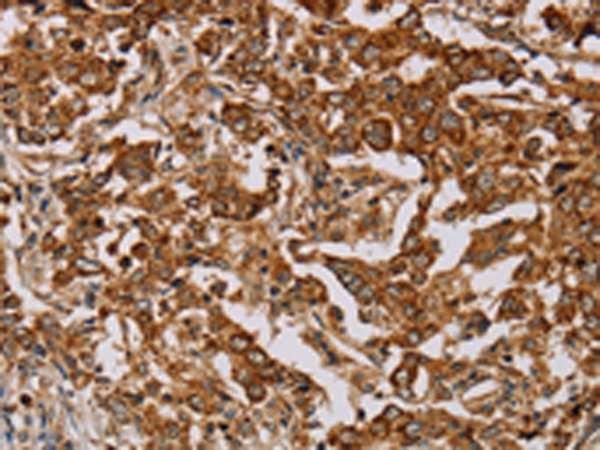

分类: 科研抗体货号: P08529别名: ZRF; MTF-1应用: IHC反应种属: Human